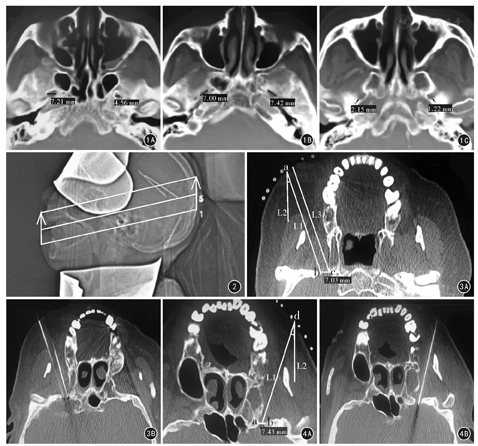

测量方法:使用日本东芝公司Aquilion 64排螺旋CT机行头颅CTA。扫描参数:扫描基线为听眦线,层厚、层距均为5 mm。在减薄层厚为0.5 mm的序列上用骨窗查找,骨窗窗宽(W)为2 000,窗位(L)为350。选取轴位图片中卵圆孔、棘孔清晰且孔径最大的层面,用CT扫描仪自带工具尺测量双侧卵圆孔的最大横径、长径,测量的起、止点为卵圆孔的骨性边缘;测量双侧卵圆孔与棘孔之间的最短距离,测量的起、止点为卵圆孔与棘孔的内壁。见图1。测量人员由同一位放射科主任医师完成。

2组患者术前均禁食4~6 h,建立静脉输液通道后仰卧在CT台上,安置生命体征监护后行CT检查。扫描参数:层厚3 mm,层距3 mm。扫描方法:在头部定位像上设定扫瞄框,行半冠状位(机架角度以扫描框与外耳道-下牙床连线平行)CT扫描;扫瞄框上缘达颧弓上缘,下缘平行重叠于外耳孔与下颌第2前磨牙牙冠连线(图2)。在CT影像上找出卵圆孔孔径最大的层面,并在该层面上设计穿刺路径。

双针双极射频组:穿刺路径设计以卵圆孔内口的内、外侧壁为穿刺靶点。由卵圆孔内口的外侧壁紧贴下颌骨冠状突向外拉一直线到皮肤表面,即口角外侧2.5~3.0 cm处,标记为外侧穿刺点;此穿刺点至卵圆孔内口外侧壁的距离为外侧穿刺深度,外侧穿刺点垂线与外侧穿刺线的夹角为穿刺角度。再由卵圆孔内口的内侧壁做前一直线的平行线到皮肤表面,标记为内侧穿刺点,此穿刺点至卵圆孔内口内侧壁的距离为内侧穿刺深度。见图3A。完成了穿刺路径设定后,对皮肤表面穿刺点进行局部麻醉。在CT定位穿刺引导器的引导下:一根射频穿刺针从外侧穿刺点紧贴下颌骨冠状突,依据测定的穿刺角度调整穿刺针的穿刺方向,穿刺至卵圆孔内口外侧壁,注意不得过于偏外侧,以防伤及距卵圆孔仅2 mm的棘孔;另一根射频穿刺针从内侧穿刺点平行于第1根穿刺针穿刺至卵圆孔内口的内侧壁处。见图3B。CT确认针尖位置,高频50 Hz、低频2 Hz电刺激试验再次确认针尖位置无误后,90 ℃射频热凝治疗120 s,针刺下颌区痛觉消失则结束治疗。

单针单极射频组:穿刺路径设计以卵圆孔内口水平横径中点为穿刺靶点。由卵圆孔内口的外侧壁紧贴下颌骨冠状突向外拉直线到皮肤表面,即口角外侧2.5~3.0 cm处,标记为穿刺点,测量穿刺点至穿刺靶点的长度为穿刺深度;穿刺点垂线与穿刺线的夹角为穿刺角度。见图4A。穿刺路径设定后,具体操步骤、治疗方法同双针双极射频组。见图4B。

200例CTA影像测量示:左右两侧卵圆孔孔径最大层面的横径分别为3.22~8.53 mm和2.62~7.73 mm、长径分别为4.29~12.77 mm和5.17~11.25 mm,卵圆孔与棘孔的最短距离分别为0.12~4.25 mm和0.17~5.13 mm,左右两侧比较差异均无统计学意义(P值均>0.05)。见表2。200例400侧卵圆孔最大横径平均5.5 mm,在本研究中作为临床患者选择的标准。

单针单极射频组,穿刺深度5.4~8.3(6.80±0.96)mm,穿刺角度14°~19°(15.81°± 1.24°);双针双极射频组,穿刺深度5.6~8.1(6.78±0.92)mm,穿刺角度14°~19°(16.01°±1.19°)。